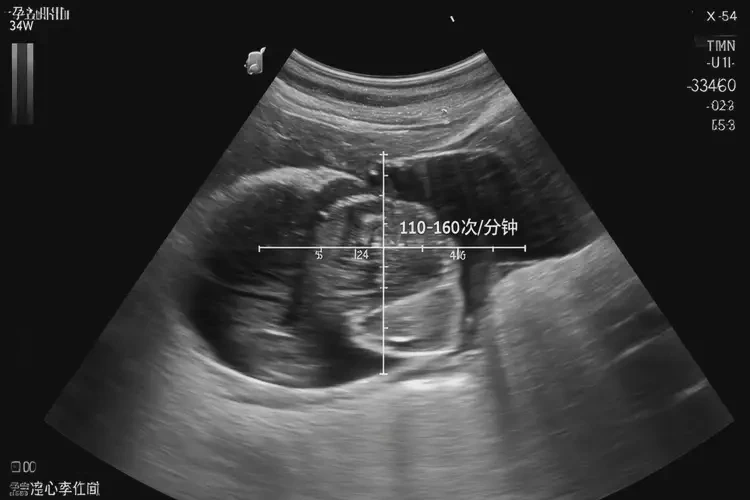

胎心100次/分鐘在孕34周5天屬于偏低范圍。正常情況下,孕34周的胎兒心率應(yīng)在110-160次/分鐘之間。胎心低于110次/分鐘可能提示胎兒宮內(nèi)缺氧或其他潛在問題,需要引起重視。

• 孕晚期(28周后):胎心率繼續(xù)保持在110-160次/分鐘的范圍內(nèi)。

孕34周5天胎心100正常嗎(圖1)